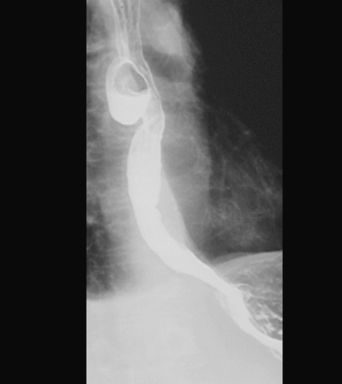

UCHYŁEK PRZEŁYKU

KONTRAST DO GOPP